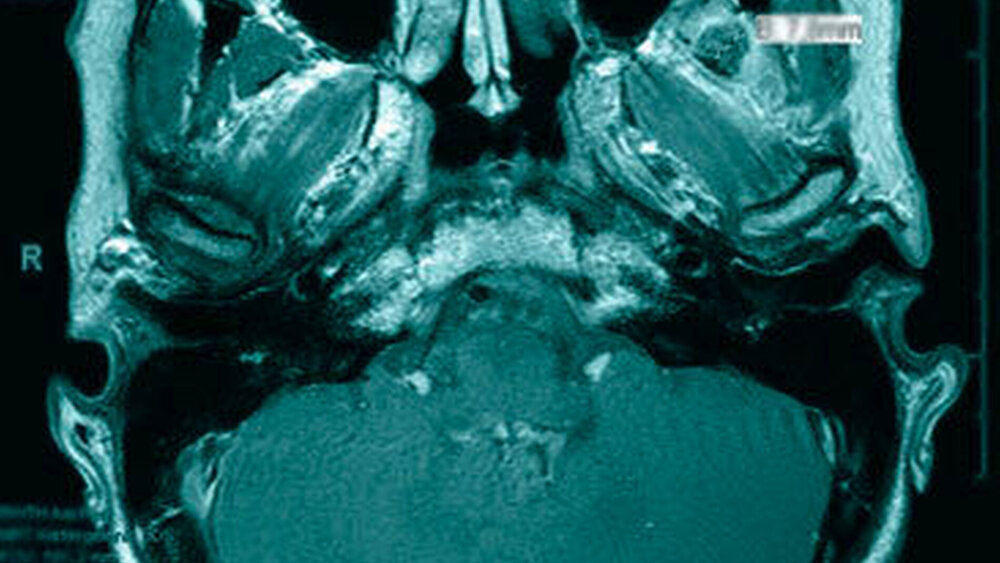

Das neun Tage später durchgeführte MRT zeigte keinen Anhalt für eine Läsion des Diskuskomplexes beidseits. Es wurde jedoch eine umschriebene, teils T2-hyperintense sowie kräftig randständig kontrastmittelaufnehmende Läsion im M. pterygoideus medialis links (axial bis zirka 1,0 cm) angrenzend an den Processus muscularis vereinbar mit einem kleinen intramuskulären Abszess beschrieben (Abbildungen 2 a und b). Des Weiteren erschien der M. pterygoideus medialis links in seinem ganzen Verlauf ödematös verändert, jedoch ohne Anhalt für eine Beteiligung der umliegenden Strukturen wie dem M. pterygoideus lateralis.